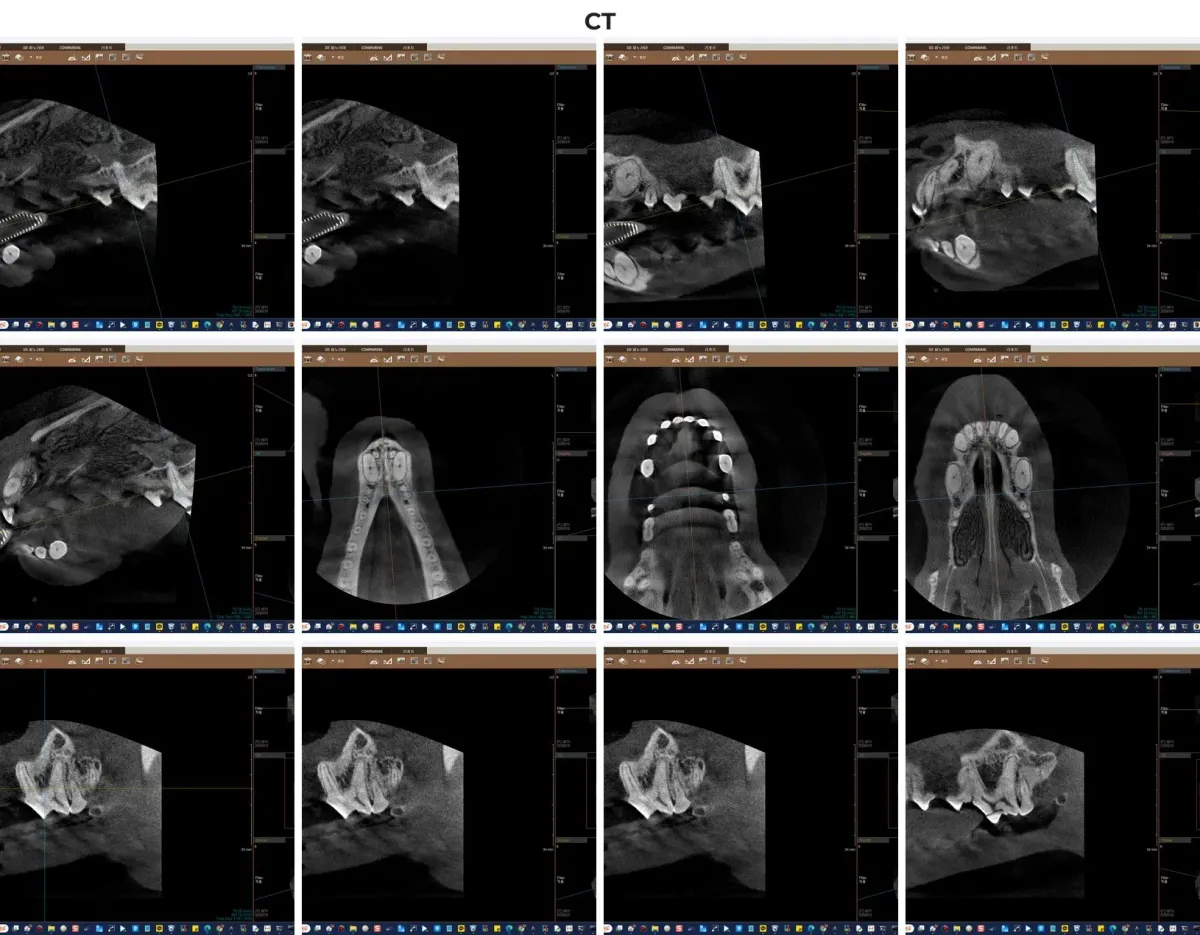

육안 검사와 더불어, 정확한 병변 파악을 위해 광주 전남 유일의 동물전용 치과 CT 촬영을 진행했습니다.

광주 금호동물병원 보유 치과 CT 촬영 이미지

• 정밀 진단: 광주 전남 유일 치과 CT를 통해 육안으로 보이지 않는 치아 내부 상태를 확인했습니다.